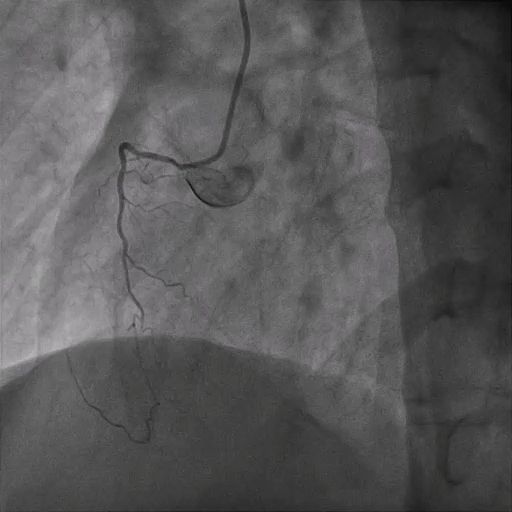

The RCA CTO had an ambiguous proximal course with a non-tapered stump and an estimated occlusion length of ≈50 mm. Distal vessel quality was good, with collateral filling mainly from the LCX, providing critical information for procedural planning and strategy selection.

Bilateral 6Fr femoral access was obtained for staged PCI to the RCA CTO. The antegrade approach using a Gaia Next 2 wire entered the mid-RCA, but ADR with a Recross microcatheter and CP12 wire failed. A retrograde approach via the PL branch was then attempted using a SUOH3 wire, with reverse CART performed using a 2.5-mm balloon and CP12 wire. The Caravel microcatheter could not cross the CTO due to lesion rigidity, and the antegrade system was lost. The retrograde system was re-established with a Turnpike 150 microcatheter, which successfully traversed the lesion and was externalized using an RG3 wire snared into the antegrade JR4 guide. During retrograde microcatheter withdrawal, the patient developed severe chest pain and hypotension (due to stretching of LV i.e., billowing), requiring stabilization with intravenous adrenaline and dopamine. After the antegrade microcatheter crossed the lesion, the retrograde system was withdrawn. The RCA was predilated with 2.0- and 2.5-mm balloons, then stented with overlapping 3.0/44-mm and 3.5/44-mm stents, followed by postdilation with NC 3.5- and 4.0-mm balloons. During the final IVUS run, the IVUS catheter became trapped at the proximal RCA stent; it was retrieved by cutting the catheter, inserting a V18 wire into its lumen, and withdrawing it through a 6Fr guide extension. Final angiography demonstrated well-expanded stents with TIMI 3 flow in the RCA.